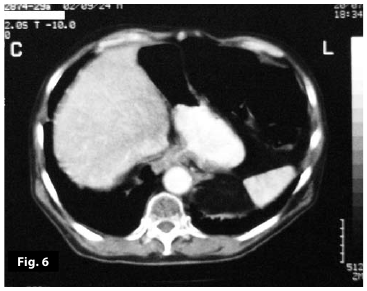

Figure6

Figure5-6